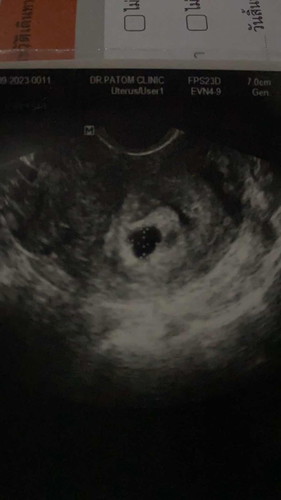

ท้องประมาณ7สับดาห์ แต่อายุครรภ์จริงๆ6สับดาห์

แม่ๆคนไหนเลยเป็นบ้างคะ ซาวครั้งแรกถ้านับตามประจำเดือนน้องจะอยู่ที่5สับดาห์ค่ะ เจอแต่ถุงเล็กมากๆ แม่กังวลมาก เพราะท้องแรกท้องลม และแท้งสมบูรณ์ค่ะ วันนี้คุณหมอนัดอัลตร้าซาว ปรากฏว่าเห็นตัวอ่อน อายุครรภ์ 6สับดาห์ มีใครเคยเป็นแบบนี้บ้างคะ แม่ๆคนไหนเป็นแบบนี้บ้างคะ#ขอบคุณสำหรับคำคอมเม้นล่วงหน้าค่ะ

#ท้องแรกคะ คุณหมอแจ้งว่า ถุงตั้งครรภ์ไม่ค่อยสวยเท่าไหร่ เสี่ยงแท้งค่ะ ช่วงนี้ก็ไม่ควร เดินหรือยืนเยอะ แม่ๆคนไหนเคยมีประสบการ์ณแบบนี้บ้างคะ